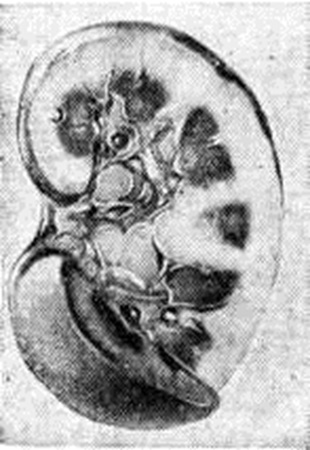

Морфологически эквивалентом протеинурии и истощения резорбтивной функции эпителия канальцев является гиалиново-капельная, вакуольная, баллонная и жировая дистрофия эпителия (цветной рисунок 1, 2, 3), при которых активность .ферментов в эпителии нефронов резко снижена (смотри полный свод знаний Дистрофия клеток и тканей). Электронно-микроскопически обнаруживаются набухание, вакуолизация и распад митохондрий, разрыв цистерн цитоплазматической сети, разрушение мембран. В результате дистрофических процессов развивается некробиоз и десквамация эпителия, которые являются основой формирования цилиндров, обтурирующих просветы канальцев, что приводит к кистозному их расширению и атрофии. Отражением функциональный недостаточности лимфатических, системы почек — второй системы реабсорбции при Нефротический синдром служит отёк интерстиция, который быстро сменяется склерозом, причём среди разрастаний соединительной ткани часто встречаются большие светлые клетки с пенистой цитоплазмой (рисунок 2), которые считают макрофагами, фагоцитировавшими липиды. В сосудах почек находят плазматическое пропитывание и гиалиноз, склероз стенок. Первичный нефротический синдром. Морфология первичного Нефротический синдром складывается из изменений, характерных для следующих его форм: липоидный нефроз, фокальный сегментарный гломерулярный гиалиноз, мембранозный гломерулонефрит (мембранозная нефропатия), врождённый Нефротический синдром (сведения о нем см. ниже). Липоидный нефроз (синонимы: идиопатический Нефротический синдром детей, нефропатия с минимальными изменениями) описан впервые Мунком (F. Munk, 1913), который обнаружил в моче больных и в эпителии канальцев липиды. Он полагал, что изменения в почках связаны с общими нарушениями обмена. Долгое время термины «липоидный нефроз», «мембранозный гломерулонефрит», «второй тип нефрита Эллиса», «нефротический синдром» употреблялись как синонимы. Благодаря работам Джонса (D. В. Jones, 1957) было выделено несколько форм Нефротический синдром: минимальные гломерулярные изменения, мембранозный гломерулонефрит и лобулярный гломерулонефрит. Название «липоидный нефроз» было оставлено только для обозначения своеобразной патологии детей, проявляющейся Нефротический синдром с минимальными изменениями в клубочках почек, выявляемых при светооптическом исследовании. Термины «липоидный нефроз» и «минимальные изменения» стали использоваться как синонимы. Сущность минимальных изменений установлена с помощью электронной микроскопии материала биопсии почек. При липоидном нефрозе изменяются только подоциты, у которых происходит слияние малых отростков, базальная мембрана при этом остаётся неизменённой (рисунок 3, а). После нескольких лет болезни к минимальным изменениям присоединяется очаговое утолщение базальных мембран капилляров (рисунок 3, б), увеличение мезангиального матрикса или количества мезангиальных клеток. Если заболевание ведёт к почечной недостаточности, в клубочках обнаруживают фокальный сегментарный склероз капилляров. В эпителии проксимальных канальцев на ранних стадиях болезни выявляют двоякопреломляющие липиды и гранулы резорбированного белка. Со временем липиды исчезают из эпителия, появляются признаки атрофии канальцев, которая никогда не бывает значительной. Интерстиций ночек отёчен, к отеку присоединяется разрастание соединительной ткани, в которой находят пенистые клетки. При длительном течении болезни встречается утолщение внутренней оболочки сосудов. Вид почек при липоидном нефрозе, протекающем без почечной недостаточности, характерен: они увеличены, очень бледные, поверхность их гладкая, на разрезе ткань набухшая, отёчная, жёлто-белая или бледно-серая — большая белая почка (смотри полный свод знаний Гломерулонефрит). В случаях смерти от почечной недостаточности почки немного уменьшены, плотные, поверхность их гладкая; ткань почек серого цвета, на разрезе выявляется жёлтая пятнистость. Фокальный сегментарный гломерулярный гиалиноз (очаговый склерозирующий гломерулонефрит) характеризуется преимущественным поражением юкстамедуллярных клубочков. Характерные для него изменения в виде сегментарного склероза впервые были описаны Ричем (A. R. Rich, 1957) у детей с липоидным нефрозом. Позднее Хабиб (R. Habib) с соавторами (1971) предложили для названия этих изменений термин «сегментарный гиалиноз». В процесс вовлекаются отдельные юкстамедуллярные клубочки (фокальные изменения), в которых склерозируются отдельные сегменты сосудистого пучка (сегментарные изменения); остальные клубочки интактны. В начале заболевания на светооптическом уровне изменения оцениваются как минимальные; электронно-микроскопически в материале биопсии почки находят характерные изменения базальной мембраны капилляров: неровные контуры эндотелиальной поверхности базальной мембраны (рисунок 4, а). При выраженной морфологический картине в отдельных капиллярах клубочков появляется гиалиновый материал в виде шаровидных отложений, обычно тесно связанных с капсулой клубочка (рисунок 4, б). В клубочках обнаруживаются пенистые клетки — мезангиальные клетки, содержащие липиды (рисунок 4, в) такие же клетки появляются и в интерстиции. При иммуногистохимическом исследовании в капиллярах клубочков находят IgM, поэтому не исключают участия первичного иммунного механизма в развитии гломерулярных изменений. По мере усиления интенсивности болезни в процесс вовлекаются клубочки поверхностных отделов коркового вещества. Сначала развивается склероз отдельных сосудистых петель, затем он охватывает все сосудистые петли клубочка (глобальный склероз). В канальцах находят жировую и белковую дистрофию эпителия, гиалиновые цилиндры в просветах, встречаются мелкие очаги кальцификации. Патогномонично образование очагов коллапса и атрофии канальцев, сопровождающееся склерозом стромы. Распространённость изменений канальцев пропорциональна выраженности изменений в клубочках. Макроскопический вид почек тот же, что и при липоидном нефрозе. Мембранозный гломерулонефрит характеризуется различными морфологический изменениями (смотри полный свод знаний Гломерулонефрит). Вторичный нефротический синдром. Морфологической основой вторичного Нефротический синдром является гломерулонефрит, который может быть первичный или вторичный (при малярии, лейшманиозе, бактериальном эндокардите, ревматизме, системной красной волчанке, узелковом периартериите, геморрагическом васкулите, нефропатии беременных, гепатите, циррозе печени, тромбозе почечных вен, опухолях и так далее). По своему генезу в большинстве случаев это иммунокомплексный гломерулонефрит, обычно с подострым и хроническим, иногда острым течением. Гистологически при таком гломерулонефрите выявляются различные типы, однако преобладают экстракапиллярный продуктивный, мембранозный, мезангиокапиллярный и фибропластический; определённую специфику имеет волчаночный нефрит. Гломерулонефрит антительного генеза при Нефротический синдром встречается редко, прежде всего при синдроме Гудпасчера. В таких случаях при гистологический исследовании находят пролиферативный экстра или интракапиллярный типы гломерулонефрита. При Нефротический синдром, осложняющем гломерулонефрит любого генеза, резко выражены дистрофические изменения канальцев, слущивание эпителия, образование цилиндров. В тех случаях, когда резко выражена гидропическая дистрофия канальцевого эпителия, принято говорить о гидропическом нефрозе. Его описывали при туберкулёзе, эндокринопатиях, авитаминозах, голодании, но особенно часто при хронический поражениях кишечника, сопровождающихся диареей (нефроз кишечного истощения). При хроническом пиелонефрите развитие Нефротический синдром связано не столько с тубулоинтерстициальными изменениями, сколько с инвазивным гломерулитом, ведущим к тяжёлым изменениям базальной мембраны и подоцитов гломерулярного фильтра. Амилоидоз (смотри полный свод знаний), как и гломерулонефрит, одинаково часто является основным морфологический проявлением вторичного Нефротический синдром, причём именно нефропатический тип амилоидоза (амилоидоз почек, или амилоидный нефроз), независимо от того, является ли он первичным, генетическим, или вторичным. Развитие Нефротический синдром при амилоидозе связано с появлением амилоидного вещества в гломерулярном фильтре, при этохамилоидобластами, продуцирующими белок фибрилл амилоида, становятся мезангиальные клетки. Появлению амилоида в клубочках предшествует амилоидоз и склероз мозгового вещества и пограничного слоя почек, что ведёт к выключению и атрофии глубоко расположенных нефронов, редукции путей юкстамедуллярного кровотока и пирамидного лимфотока. Развивается гиалиново-капельная или вакуольная дистрофия эпителия канальцев: почки увеличиваются в размерах, становятся плотными; поверхность их бледно-серая или жёлто-серая. На разрезе корковое вещество широкое, матовое, мозговое вещество серо-розовое, сального вида (большая сальная почка — рисунок 5). При нарастании протеинурии и переходе протеинурической стадии амилоидоза почек в нефротическую стадию количество амилоида в почках увеличивается. Он обнаруживается во многих капиллярных петлях большинства клубочков, в артериолах и артериях, по ходу собственных мембран канальцев, но выраженные склеротические изменения коркового вещества отсутствуют. В пирамидах, наоборот, склероз и амилоидоз имеют диффузный характер. В эпителии канальцев наряду с гиалиново-капельной и вакуольной отмечается жировая дистрофия. В эпителии канальцев и строме много двоякопреломляющих липидов (холестерина). Канальцы расширены, забиты цилиндрами. Почки становятся большими, плотными, восковидными (большая белая амилоидная почка). Эти морфологический изменения характеризуют так называемый амилоиднолипоидный нефроз, а правильнее — нефротическую стадию амилоидоза почек. Диабетический гломерулосклероз (смотри полный свод знаний Гломерулосклероз диабетический) представляет собой одно из наиболее ярких проявлений диабетической микроангиопатии. В основе его лежит пролиферация мезангиальных клеток в ответ на засорение гломерулярного фильтра и мезангия, а также повышенное образование клетками мембраноподобного вещества. Склероз капиллярных петель может носить диффузный или очаговый характер, что послужило основанием для выделения диффузной, узловатой и смешанной форм диабетического гломерулосклероза. Гломерулосклероз нередко дополняется экссудативными проявлениями диабетической нефропатии в виде «фибриновых колпачков» на капиллярных петлях и «капсульной капли», а также гликогенной «инфильтрацией» эпителия узкого сегмента нефрона, где происходит полимеризация глюкозы в гликоген. Парапротеинемический нефроз (синонимы: миеломная нефропатия, миеломная почка), развивающийся в связи с наличием парапротеинемии и парапротеинурии, характеризуется прежде всего нарастающей дистрофией (гиалиново-капельная, вакуольная) и гибелью эпителия канальцев преимущественно проксимального сегмента, обилием цилиндров и кристаллов белка в канальцах, что ведёт к их обструкции, нарастающему нефрогидрозу, лимфостазу и повышению внутрипочечного давления. Как реакция на эти изменения возникает склероз и гиалиноз стромы, восходящий от пирамид к корковому веществу почек, что завершается перигломерулярным склерозом и нарастающей гибелью нефронов. Иногда к этим изменениям присоединяется параамилоидоз. Симптоматика и течениеЖалобы больных — слабость, анорексия, жажда, сухость во рту, отеки, ощущение тяжести в поясничной области. Отеки развиваются быстро, сопровождаясь олигурией, и могут достигать степени анасарки, сочетаться с водянкой полостей (асцит, гидроторакс, гидроперикард), но могут и отсутствовать. При больших отёках на бледной коже появляются полосы растяжения, признаки дистрофии кожи и её дериватов — волос, ногтей: шелушение, сухость, ломкость. При нарастании гидроторакса и гидроперикарда появляется одышка при физической нагрузке и в покое. При отсутствии асцита удаётся пальпировать увеличенную печень мягкоэластической консистенции. Тоны сердца могут быть приглушены, при анемии возникает тахикардия и систолический шум. По мере уменьшения отёков выявляется атрофия скелетной мускулатуры. Функция щитовидной железы может быть снижена. К этим клинические, признакам добавляются проявления основного заболевания, что крайне отягощает состояние больного. По характеру течения выделяют три варианта невротического синдрома: эпизодический, появляющийся лишь в начале основного заболевания с исходом в ремиссию или рецидивирующий, чередующийся с ремиссиями (функция почек при этом в течение 10—20 лет сохраняется нормальной); персистирующий, когда Нефротический синдром сохраняется, несмотря на лечение, в течение 4—8 лет без снижения функций почек (соответствует прежнему понятию «хронический нефроз»); прогрессирующий с переходом за 1 — 3 года в стадию хронической почечной недостаточности. Вариант течения в определённой мере зависит от нозологической формы Нефротический синдром и морфологический особенностей нефропатии. Так, эпизодическое течение свойственно аллергическому Нефротический синдром; быстропрогрессирующее течение, помимо экстракапиллярного первичного гломерулонефрита, наблюдается при фокально-сегментарном гломерулярном гиалинозе. У лиц пожилого возраста чаще встречаются второй и третий варианты течения. ОсложненияПри Нефротический синдром развиваются разнообразные и многочисленные осложнения: отёк мозга, сетчатки глазного дна, нефротический криз (гиповолемический шок), флеботромбозы, вторичная инфекция, инфаркт миокарда, инсульт головного мозга, острая почечная недостаточность и другие В период лекарственной терапии количество осложнений может резко увеличиться, так как некоторые препараты при Нефротический синдром могут оказывать токсическое, аллергическое действие, а также провоцировать отдельные симптомы Нефротический синдром (например, в период стероидной терапии может усилиться гиперкоагуляция и развиться тромбоз). ДиагнозДиагноз при ярко выраженной клинические, симптоматике Нефротический синдром не вызывает затруднений. Важное значение в диагностике имеют лабораторный методы исследования. Наиболее частый лабораторный признак при Нефротический синдром— большая протеинурия (смотри полный свод знаний). Количество белка иногда достигает 20—50 грамм/суток. Белки, определяемые в моче, плазменного происхождения, однако с противоположным соотношением по молекулярному весу: в моче — максимальное количество альбумина, относительно увеличено содержание α1 и β-глобулинов и понижено (иногда до следов) α2-и γ-глобулинов. Состав белков мочи и селективность протеинурии зависят от характера основного заболевания. Неселективный характер протеинурии, то есть выделение высокомолекулярных белков, отражает большую тяжесть поражения нефрона. Однако не селективность протеинурии может быть обратимой. Выделение с мочой больших количеств таких ферментов, как трансамидиназа, лейцинаминопептидаза, кислая фосфатаза, (β-глюкуронидаза, N-ацетилглюкозоаминидаза и другие свидетельствует об остром процессе в почках, о тяжести поражения нефрона, особенно эпителия извитых канальцев, о высокой проницаемости клеточных мембран. Кроме того, в моче больных с Нефротический синдром определяют до 5 электрофоретических фракций гликопротеидов и 2—3 фракции липопротеидов. Характерна для Нефротический синдром и гипераминоацидурия, особенности которой зависят скорее от основного заболевания (смотри полный свод знаний Аминоацидурия). Гипопротеинемия (смотри полный свод знаний Протеинемия) — постоянный симптом Нефротический синдром Общий белок крови снижается до 4,0 и даже 3,0 грамм/100 миллилитров, в связи с чем онкотическое давление плазмы падает с 30—40 до 10—15 сантиметров водного столба. В происхождении этого признака, помимо потери белков с мочой, имеет значение ещё и усиленный катаболизм их (в частности, альбумина), перемещение некоторых белков во внеклеточную жидкость, потеря их через отёчную слизистую оболочку кишечника, снижение синтеза белков в печени и так далее Диспротеинемия, неизменно сопутствующая гипопротеинемии, выражается в резком уменьшении концентрации альбумина в сыворотке крови, повышении α2 и β-глобулиновых фракций. Содержание гамма-глобулинов чаще снижено, хотя при некоторых заболеваниях может быть и повышено. В α2-глобулиновой фракции повышено содержание гаптоглобинов и α2-макроглобулина. При этом повышается и содержание фибриногена, синтез которого находится в прямой зависимости от количества гаптоглобина. При значительно выраженном Нефротический синдром изменяется соотношение в сыворотке крови содержания основных классов иммуноглобулинов: снижаются иммуноглобулины классов А и G и повышается уровень иммуноглобулинов класса М. Уровень сывороточного комплемента (по гемолитической активности) снижается в разной мере — более резко при волчаночном Нефротический синдром, реже — при Нефротический синдром амилоидного происхождения. Гиперлипидемия — также типичный признак Нефротический синдром Проявляется повышенным содержанием холестерина, триглицеридов и фосфолипидов, дислипопротеидемией (смотри полный свод знаний Липопротеиды). Увеличивается концентрация пребета и бета-липопротеидов при нормальном или пониженном количестве альфа-липопротеидов. Гиперлипидемия связана с рядом причин: задержкой липопротеидов как высокомолекулярных веществ в сосудистом русле, усиленным синтезом холестерина в печени, снижением активности липолитических ферментов (липопротеидлипазы), возможно, нарушением метаболической функции почек. В тесной связи с гиперлипидемией находится липидурия, которая определяется по наличию жировых цилиндров в моче, иногда жира, лежащего свободно или внутри слущённого эпителия. Кроме того, при Нефротический синдром наблюдается гиперкоагуляция крови — от небольшой степени активации свёртывающей системы крови до предтромботического состояния и криза локальной или диссеминированной внутрисосудистой коагуляции. Этим нарушениям гемостаза (смотри полный свод знаний) способствует состояние депрессии системы фибринолиза и снижение антикоагулянтной активности крови. Лишь в крайне редких случаях при Нефротический синдром удаётся наблюдать высокую фибринолитическую активность. Факторами, способствующими гиперкоагуляции, являются снижение уровня таких ингибиторов протеиназ, как антитромбин-III, альфаантитрипсин; при повышении уровня главного антиплазмина — альфа2-макроглобулина, а также усиление адгезивных свойств тромбоцитов. Отмечаются электролитные сдвиги в сыворотке крови (снижение концентрации кальция, калия), гиповитаминоз (особенно недостаточность витаминов С и D), изменения содержания микроэлементов. Гуморальные нарушения сказываются на метаболизме и функциональный состоянии лейкоцитов крови. Так, в лимфоцитах крови снижается активность окислительно восстановительных ферментов (сукцинат- и альфа-глицерофосфат — дегидрогеназ), в нейтрофилах изменяется активность щелочной и кислой фосфатаз. У многих больных выявляется анемия, гипертромбоцитоз и ускоренная РОЭ. В мочевом осадке, помимо эритроцитов, могут определяться в значительном количестве лимфоциты (10—60%). Наряду с гиалиновыми цилиндрами при Нефротический синдром обнаруживают и восковидные, что соответствует большой протеинурии. Дифференциальный диагноз основан главным образом на данных биопсии почки и других органов и тканей (кожи, десны, слизистой оболочки прямой кишки, печени), а также пункции грудины (при подозрении на миеломную болезнь). Имеют значение и некоторые лабораторный методы (анализ на LE-клетки и титр антител к ДНК при подозрении на системную красную волчанку и так далее). ЛечениеНеобходимы ранняя госпитализация, быстрая дифференциальная диагностика с попыткой воздействия на инициальные и ведущие механизмы основного заболевания. Назначается бессолевая, богатая калием диета с содержанием животного белка 1 грамм/килограмм веса больного. Большие белковые нагрузки приводят к росту протеинурии и угнетению фибринолитической системы крови. Учитывая гипоальбуминемию, при Нефротический синдром суточные дозы лекарственных препаратов должны быть полуторными или двойными, распределёнными для приёма дробно; при выраженном отёке их лучше вводить внутривенно. Стероидная терапия показана при Нефротический синдром лекарственной, волчаночной этиологии, мембранозном гломерулонефрите. Цитостатики (имуран, циклофосфамид или лейкеран) назначают больным с Нефротический синдром, имеющим противопоказания для стероидной терапии или при её неэффективности. Отмечен особенно хороший эффект в результате их применения при лечении Нефротический синдром у больных узелковым периартериитом, синдромом Вегенера. Их нередко назначают в сочетании с кортикостероидами. Антикоагулянты (гепарин 20—50 тысяч ЕД в 1 суток в течение 4—6 недель, нередко в сочетании с курантилом, иногда с непрямыми антикоагулянтами) показаны и эффективны при всех нозологических и морфологический формах Нефротический синдром, при которых выражен механизм внутрисосудистой коагуляции. Противовоспалительные средства (индометацин, бруфен) показаны для лечения больных мембранозным и мезангиопролиферативным гломерулонефритом с Нефротический синдром Из симптоматических средств при Нефротический синдром употребляют мочегонные (салуретики, антагонисты альдостерона), дозы которых подбирают индивидуально. Хороший эффект можно ожидать при сочетании лазикса с раствором обессоленного альбумина или реополиглюкина внутривенно. При лечении резистентных отёков у больных с олигурией могут быть применены ультрафильтрация (смотри полный свод знаний) и гемофильтрация (смотри полный свод знаний). Рекомендуется санаторно-курортное лечение (Байрам-Али, Бухара, а в период ремиссии — курорты Южного берега Крыма). Показания к курортному лечению зависят от основного заболевания и степени его активности. ПрогнозПрогноз при Нефротический синдром зависит от многих факторов: возраста, характера основного заболевания, особенностей нефропатии, морфологический особенностей (ремиссий не бывает при фибропластическом варианте), длительности Нефротический синдром, клинические, формы, адекватности лекарственной терапии и другие Причины смертельных исходов: прогрессирующее течение основного заболевания и (или) нефропатии как основного проявления этого заболевания; почечная недостаточность (острая или хроническая); инфекционные осложнения (пневмония, эмпиема плевры, сепсис, апостематозный нефрит); тромбоэмболии; агранулоцитоз; желудочно-кишечные кровотечение и другие ПрофилактикаМеры специфической профилактики развития Нефротический синдром не разработаны. Определённое значение могут иметь раннее и успешное лечение заболеваний, осложняющихся Нефротический синдром, а также диспансеризация больных. Врождённый (семейный) нефротический синдромВрождённый (семейный) нефротический синдром объединяет группу заболеваний, при которых отеки появляются в первые недели жизни ребёнка в связи с развитием у него изменений в почках ещё в антенатальном периоде. Нефротический синдром иногда имеет семейный характер и нередко наследуется. Наибольшее распространение Нефротический синдром отмечалось в Финляндии (заболеваемость среди новорожденных до 1980 год составляла 1 на 10 000 родившихся). В других странах, в том числе и в СССР, заболевание встречается значительно реже. Особенности клинико-морфологических проявлений Нефротический синдром у детей в Финляндии дало основание для выделения так называемый врождённого Нефротический синдром финского типа, представляющего собой генетически детерминированный вариант патологии, наследуемый по аутосомно-рецессивному типу. Предполагается, что мутация впервые произошла около 400 лет тому назад в одном из северно-западный районов Финляндии, который в течение многих лет имел характерные черты изолята, где были нередки родственные браки. Рождению ребёнка с Нефротический синдром предшествует тяжело протекающая беременность. При этом выявляются иммунологический феномены несовместимости между матерью и плодом (в крови у матери и ребёнка обнаружены преципитирующие антитела, направленные против антигенов почек плода и плаценты). Роды нередко преждевременные, плацента увеличена и составляет более 25% веса тела новорожденного. Врождённый Нефротический синдром финского типа проявляется с первых дней жизни ребёнка (реже — после 2 месяцев) и характеризуется выраженными отёками, протеинурией, тяжёлой гипопротеинемией с резкой гипогаммаглобулинемией. Такие дети отстают в физическом развитии, у них выражены стигмы дизэмбриогенеза (деформация ушных раковин, синдактилия, гипертелоризм, грыжи и другие); они гипотрофичны, а динамичны, подвержены инфекционным болезням и другим заболеваниям, сопровождающимся септическими осложнениями, которые, как правило, являются причиной летального исхода. При гистологический исследовании почек выявляются чёткообразные цепочечные расширения проксимальных отделов нефрона (псевдокистоз), обнаруживаются различной степени выраженности гломерулярные, тубулярные и интерстициальные изменения, степень которых нарастает по мере прогрессирования заболевания, а также большое количество фетальных гломерул и гломерул с увеличенным диаметром. Врождённый Нефротический синдром, встречающийся у детей спорадически (в других странах), выявляется, как правило, в более позднем возрасте (нередко в конце первого или на втором году жизни), течение его более лёгкое. В отличие от врождённого Нефротический синдром финского типа в почках при этом могут наблюдаться следующие варианты морфологический изменений: мезангиальный диффузный склероз, фокальный или сегментарный гиалиноз и гломерулонефрит с экстрамембранной локализацией па то л. процесса; микрокистоз наблюдается реже. Диагноз врождённого Нефротический синдром не представляет трудности и основан на данных анамнеза, типичной клинические, картине, данных лабораторных исследований и биопсии почки. Лечение не разработано. Применение глюкокортикоидных гормонов и иммунодепрессантов неэффективно и нередко утяжеляет течение синдрома. Уменьшение анасарки иногда достигается применением диуретиков. В Финляндии было проведено несколько операций по пересадке почки детям до одного года с Нефротический синдром, но они не дали положительных результатов. Прогноз неблагоприятный. Дети погибают от интеркуррентных заболеваний или почечной недостаточности. Профилактика не разработана. Имеются данные о возможности антенатальной диагностики путём определения а-фетопротеина в амниотической жидкости. В случае положительной реакции рекомендуется прерывание беременности. Экспериментальный нефротический синдромМодели Нефротический синдром позволяют уточнить его патогенетические механизмы и воспроизвести ряд изменений почек, характерных для этого синдрома. Адекватной моделью первичного Нефротический синдром считают аминонуклеозидный нефроз. Эта модель морфологически наиболее близка липоидному нефрозу, так как, по данным Фаркар (М. G. Farquhar) и Дж. Пелейда, основные изменения при введении аминонуклеозида возникают в эпителии гломерулярного фильтра: подоциты теряют малые отростки, вакуолизируются, в цитоплазме их появляется большое количество белковых гранул; повреждается щелевидная мембрана. Кефалидес, Форселл-Нотт (N. A. Kefalides, L. Forsell-Knott) установили, что базальная мембрана гломерулярного фильтра изменяется вторично, теряет гидроксилизин, гидроксипролин и глицин; электронно-микроскопически находят изменения её макромолекулярной структуры. Она становится повышенно проницаемой для крупномолекулярных белковых частиц (каталаза, ферритин). Моделями вторичного Нефротический синдром можно считать экспериментальные грамм ломерулонефрит и амилоидоз, а также поражения почек, возникающие у подопытных животных под воздействием некоторых органических и неорганических веществ. Для воспроизведения в эксперименте гломерулонефрита, сопровождающегося Нефротический синдром, используют разные воздействия: однократное или повторное парентеральное введение гетеро или гомологичного белка, сенсибилизацию чужеродным белком и создание условий локализации гиперергической реакции (инфекции) в почках, микроорганизмы и их токсины, а также смеси бактериальных антигенов с гомологичной почечной тканью, антипочечную цитотоксическую сыворотку, гомологичную или аутологичную ткань почки. Эти эксперименты позволили доказать роль иммунологический повреждения (циркулирующие иммунные комплексы, антипочечные антитела) базальной мембраны клубочковых капилляров в развитии Нефротический синдром Циркулирующие иммунные комплексы находят в таких случаях электронно-микроскопически на эпителиальной стороне базальной мембраны; при повреждении её антителами обнаруживают характерные изменения, подобные тем, которые возникают при пневморенальном синдроме Гудпасчера. При экспериментальном амилоидозе, для воспроизведения которого обычно вводят казеин, показана роль глубоких обменных нарушений (белка, липидов) в развитии Нефротический синдром Классические проявления амилоидного Нефротический синдром (или нефроза) в виде мочевого синдрома, гипопротеинемии, гиперлипидемии, отёков обнаруживают на 6—8-й недель опыта (нефротическая стадия), когда амилоид «загружает» не только пирамиды, но и клубочки, а дистрофия канальцев и лимфостаз достигают максимума. В основе развития Нефротический синдром в этих случаях, по мнению В. В. Серова, лежит первичное повреждение амилоидом гломерулярного фильтра и вторичная недостаточность тубулолимфатического аппарата реабсорбции почек. На моделях повреждения почек некоторыми органическими и особенно неорганическими (ртуть, свинец, уран) соединениями Д. С. Саркисовым, П. И. Ремезовым показано значение токсических воздействий и состояния почечных канальцев для развития Нефротический синдром Эти модели более применимы для изучения механизмов острой почечной недостаточности.